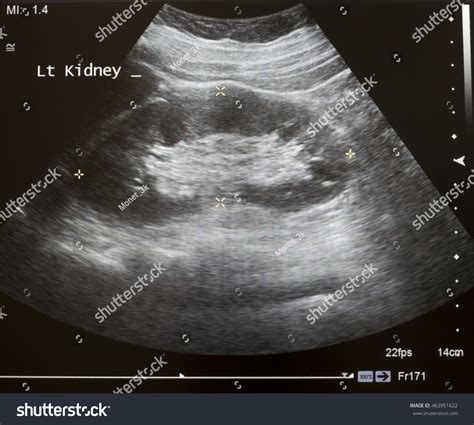

A kidney ultrasound, or sonography, uses high-frequency sound waves to create images of the kidneys, ureters, and bladder. It is frequently the first line of investigation for clinicians because it is safe, widely available, and highly effective at identifying structural abnormalities. When a radiologist reviews the images, they are looking for specific markers that indicate health versus disease.

When you receive a report stating you have a Normal Ultrasound Of Kidneys, it means that the radiologist has evaluated several specific parameters and found them to be within expected clinical ranges. The kidneys are evaluated for their size, shape, position, and internal architecture. If these elements match the standard anatomical profile for a healthy adult, the organ is considered functioning structurally as intended.

The term Normal Ultrasound Of Kidneys is standardized by medical imaging professionals. During the procedure, the sonographer maneuvers a transducer over your abdomen and back, capturing images from multiple angles. The following table summarizes what clinicians identify as normal characteristics compared to potential abnormal findings.

Preparing for a kidney ultrasound is relatively simple. In many instances, you may be asked to arrive with a full bladder, as this can help provide a better acoustic window for imaging the lower poles of the kidneys and the bladder itself. The procedure itself is painless and usually takes between 15 to 30 minutes.

• You will lie on an exam table, usually on your side or stomach.

• A warm, water-based gel is applied to the skin over the kidney area.

• The sonographer slides the transducer back and forth to capture high-resolution images.

• You may be asked to hold your breath for a few seconds to prevent image blurring.